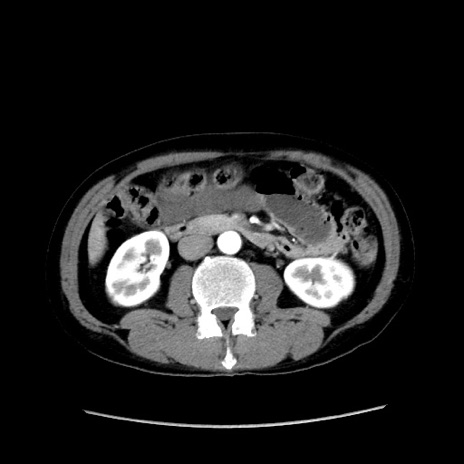

症例37(横断像)

【症例】40歳代 男性

【主訴】腹痛

【現病歴】4時間ほど前に電車に乗車中に臍部上より腹痛出現。徐々に増悪し起立困難となり、救急外来受診。生ものは数日食べていない。今朝お雑煮を食べた。

【身体所見】BT 36.8℃、BP 117/84mmHg、HR 91/min、SpO2 97%、苦悶様、腹部:臍上部広範囲圧痛あり、反跳痛±

【データ】WBC 8100、CRP 0.03